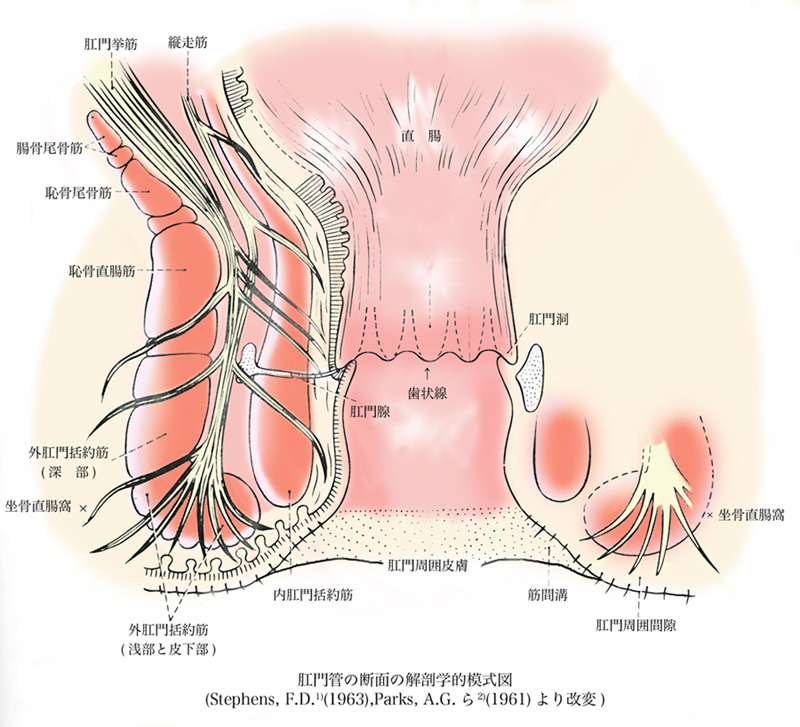

おしりの構造と病気 森外科医院 日本大腸肛門病学会認定施設 日本臨床肛門病学会認定施設 岐阜県大垣市で肛門科をお探しの方は肛門専門病院の森外科医院までご相談下さい

痔について 門田外科医院

Gastropedia ガストロペディア 消化器にかかわる医療関係者のために

痔ってなンだ 4 おしりだって風邪をひく

医療法人明信会 今泉西病院 裂肛の話

痔ろうの治療 木村病院

肛門外科 外科 診療科 部門紹介 外来受診される方 宇治武田病院 武田病院グループ

肛門 直腸の構造断面図イラスト 人体 医療 イメージマート

あなたの痔はどのタイプ 診療方法と肛門科診療のタイミング 内科 整形外科 肛門科 痔 浜中医院 大阪府岸和田市

Gastropedia ガストロペディア 消化器にかかわる医療関係者のために

肛門に多い病気